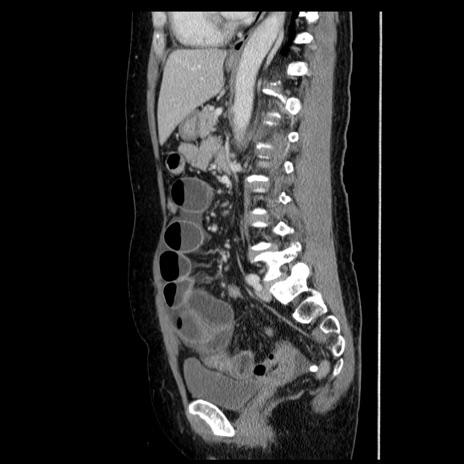

症例6(矢状断像)

症例